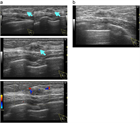

1. 30~40歳代の成熟期女性に好発する、硬結・腫瘤、疼痛、乳頭異常分泌などの症状を呈する乳腺の良性疾患である。